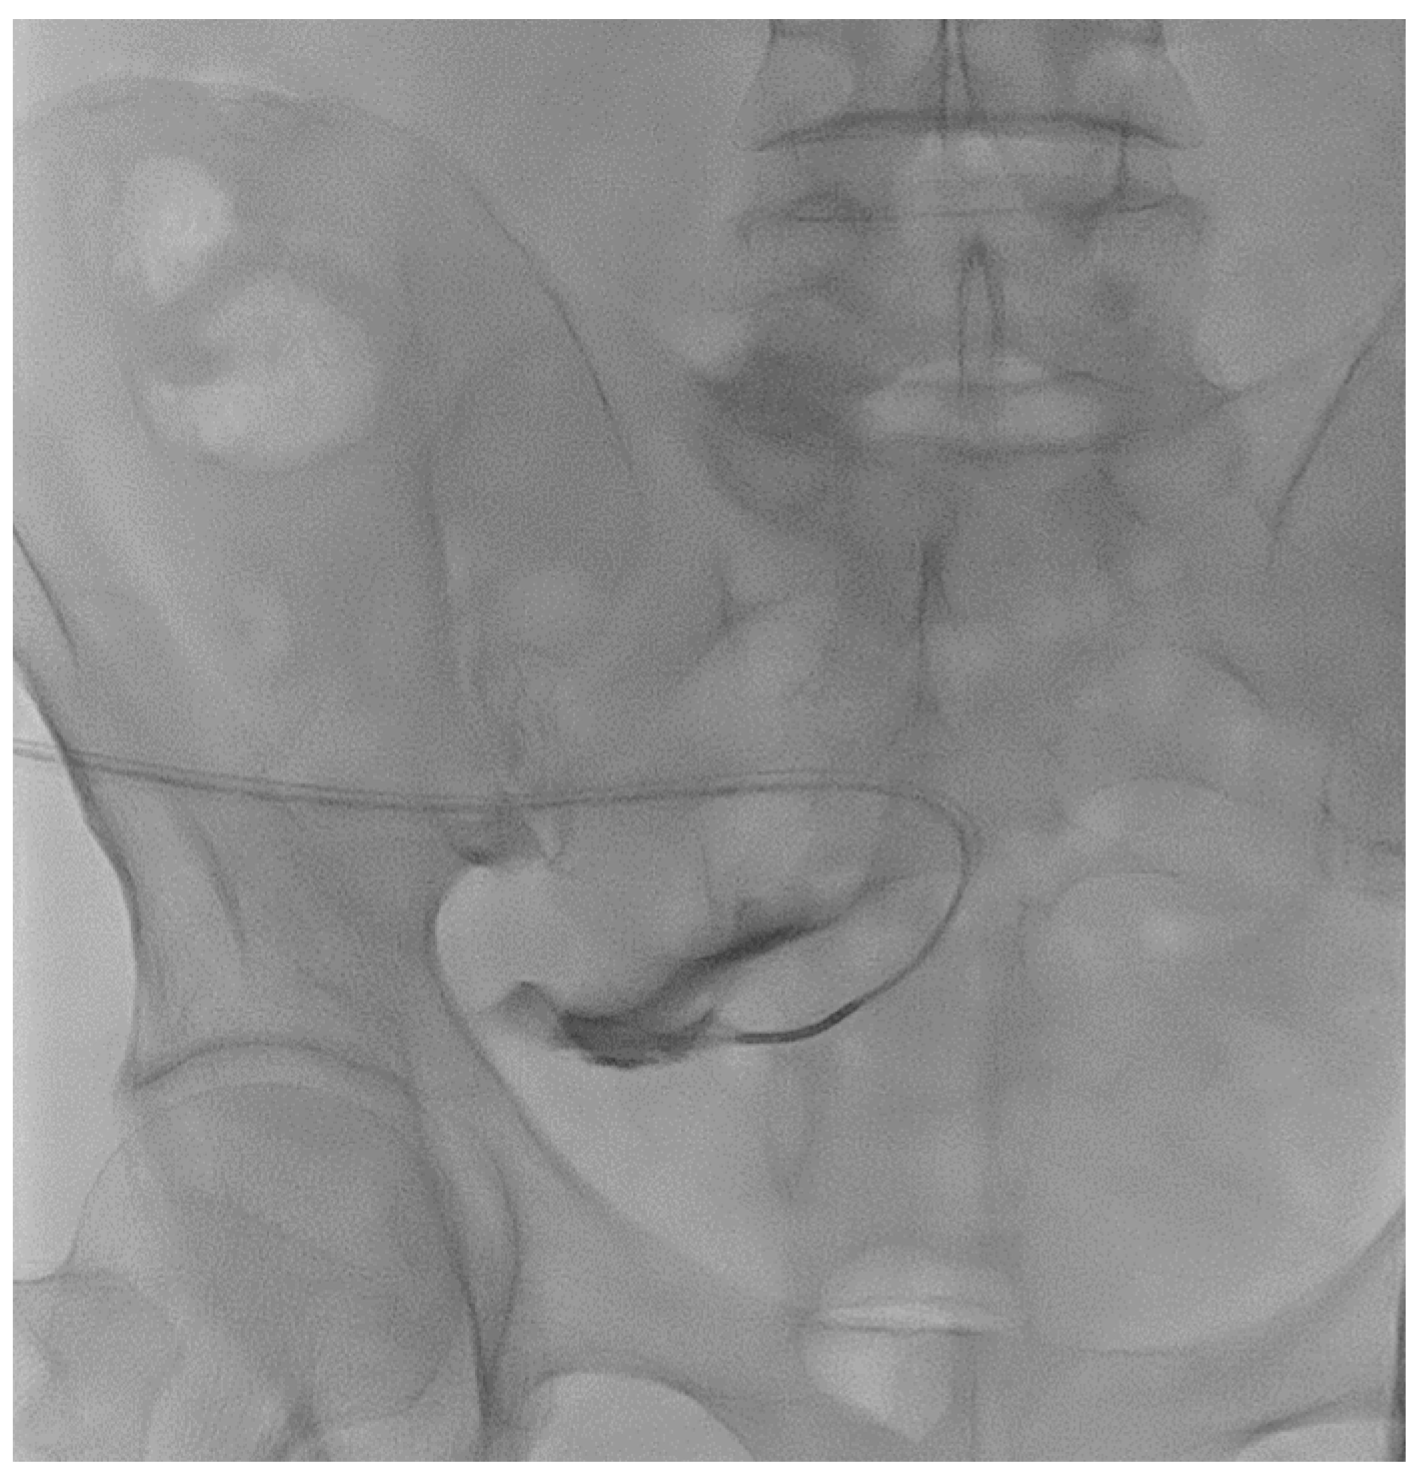

A 67-year-old male patient affected by Autosomal Dominant Tubulointerstitial Kidney Disease due to UMOD mutation (ADTKD-UMOD) in peritoneal dialysis for 15 months reported catheter malfunction since the start of peritoneal dialysis with many alarms occurring during the outflow phase of every APD cycle. The abdomen X-ray showed the correct position of the catheter tip, and laxatives did not help to reduce alarm frequency. Guidewire manipulation was successfully performed (Figure 3). The absence of spillage from the side holes made it suspicious for the presence of adhesions insinuated into the holes that may explain the drainage problems. Also, the use of the guidewire to force the movement of the catheter from its position may have helped to debride the catheter from adhesions. The patient did not report pain or any other complication of the procedure and could re-take peritoneal dialysis right afterward. One month after the procedure, the patient could still effectively perform peritoneal dialysis.

Figure 3. Catheterography showing no spillage of contrast medium from the side holes.